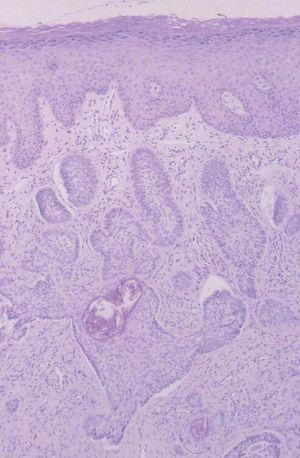

La colonoscopia fue normal y la biopsia de la lesión fue diagnóstica (fig. 2).

Fig. 2.--Proliferación neoplásica constituida por células de estirpe basal reunidas en masas y nidos sólidos, e imágenes en empalizada periférica. (Hematoxilina-eosina, x100.)

En el estudio histopatológico se observaba una epidermis ortoqueratósica y discretamente aplanada, con ulceración central, de cuya capa basal partía una proliferación neoplásica constituida por células de estirpe basal reunidas en masas y nidos sólidos e imágenes en empalizada periférica. El estroma era moderadamente desmoplásico y mostraba un infiltrado de tipo crónico (fig. 2).